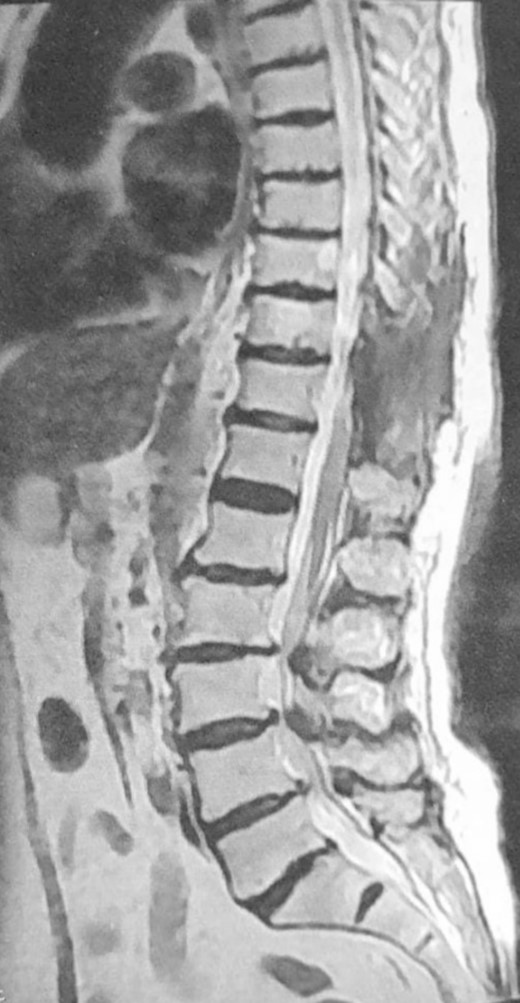

within the lesion, while T2-weighted images (T2WI) exhibited variable signal intensity, predominantly hypointense, in addition to surrounding tissue changes indicative of compression and edema (Fig. 2). Subsequently, the patient underwent surgical excision of the lesion, including laminectomy of D10–D11. A sharp dissection of the mass from the dura was performed during the surgery (Fig. 3). Two months after surgery, the patient underwent a short course of physiotherapy for several weeks, and now they can ambulate without support. The postoperative period was uneventful. Histopathological analysis revealed the presence of classical psammoma bodies, characterized by calcium deposits or punctate calcifications within the tumor mass, consistent with a diagnosis of classic meningioma ossified (Fig. 4). A follow-up MRI performed after 3 months demonstrated complete excision with no evidence of tumor recurrence (Fig. 5).

Postoperative MRI, sagittal view, T2WI, showing complete resection of the tumor.